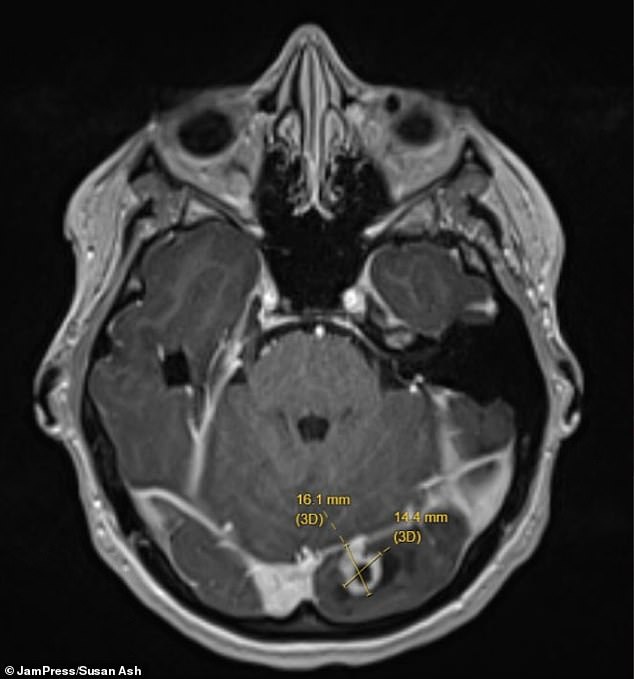

The above is a picture of the scan of Ms Ash' brain, with the tumor shown by the yellow lines.

Doctors found the tumor on her left occipital lobe — the part of the brain at the back of the head responsible for processing visual information from the right eye.

She was rushed to hospital, where imaging scans revealed a marble-sized tumor pressing on her brain.